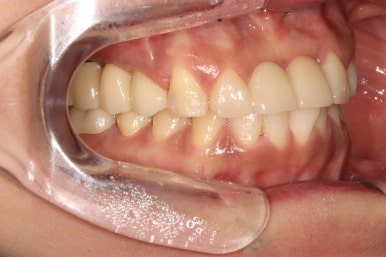

우측 측면 사진입니다.

우히려 좌측에 비해 더 예쁘게 마무리된 것 같아요~

기존에 큰 아말감 치료를 받으셨고, 이차 충치가 심해 검게 보이던 오른쪽 아래 큰 어금니는 이제 하얀 지르코니아 크라운으로 예쁜 모습을 되찾았습니다.

오른쪽 위 어금니들도 뿌리만 남아있던 잔존치근들이 모두 제거되고, 앞니와 같은 하얀색의 치아들로 완전히 대체된 모습을 보실 수 있습니다.